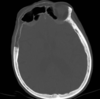

Cisto ósseo aneurismático

Acomete paciente jovem (fise aberta);

Localização excêntrica, aspecto em favo de mel no RX;

Pode ter reforço periosteal;

RM:lesão multicística; Septos + nível liquido-liquido (lesões dx diferencial: COS fraturado, COA, TCG ou osteossarcoma telangiectásico).

Primário ou Secundário à outros tumores: TCG, DF, Condroblastoma.